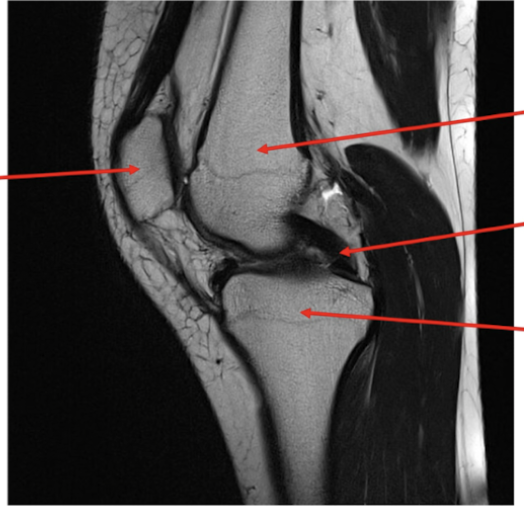

label each

2- lateral and medial condyles of femur

4- vastus lateralis muscle

5-posterior cruciate ligament

6- anterior cruciate ligament

7- medial meniscus of knee

8- lateral meniscus of knee

9-tibia

10-fibula